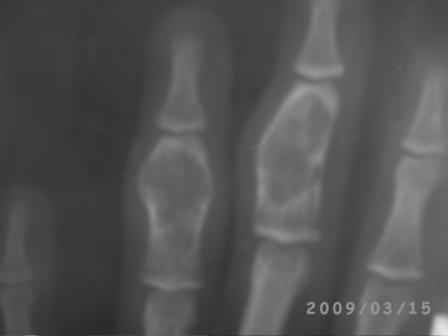

Уважаемые коллеги, на осмотре девочка 2006 г.рожд. Со слов матери 3мес. назад заметила припухлость основного фаланга 3-пальца, которая постепенно увеличилось до настоящего размера где-то в течении месяца, не болит, ребенка не беспокоит, признаки воспаления отсутствуют. Консультация онколога, биопсия - опухоль исключена (со слов матери), фтизиоортопед - тбс исключен. От основной фаланги 3 пальца к головке 4-пястной кости под кожей прощупывается хрящевидная ткань. Р-граммы от 10 декабря и 15 февраля, и фото прилагается. Что делать? Уважаемые коллеги, помогите! С уважением Абдурашид.

Добрый день, уважаемый Абдурашид. Судя по рентгенограмме, к сожалению не очень качественной, речь может идти о варианте дисхондроплазии, которую обозначают, как солитарную хондрому. Рентгенологически они проявляются в 3 вариантах-в виде интрамедуллярно и центрально расположенной энхондромы с вертеннобразным вздутием диафиза изнутри и истончением кортикальной пластинки, в виде опухоли, расположенной эксцентрично с заполнением части кортикального слоя и характерным костным козырьком, в виде экхондром, выступающих за пределы кости